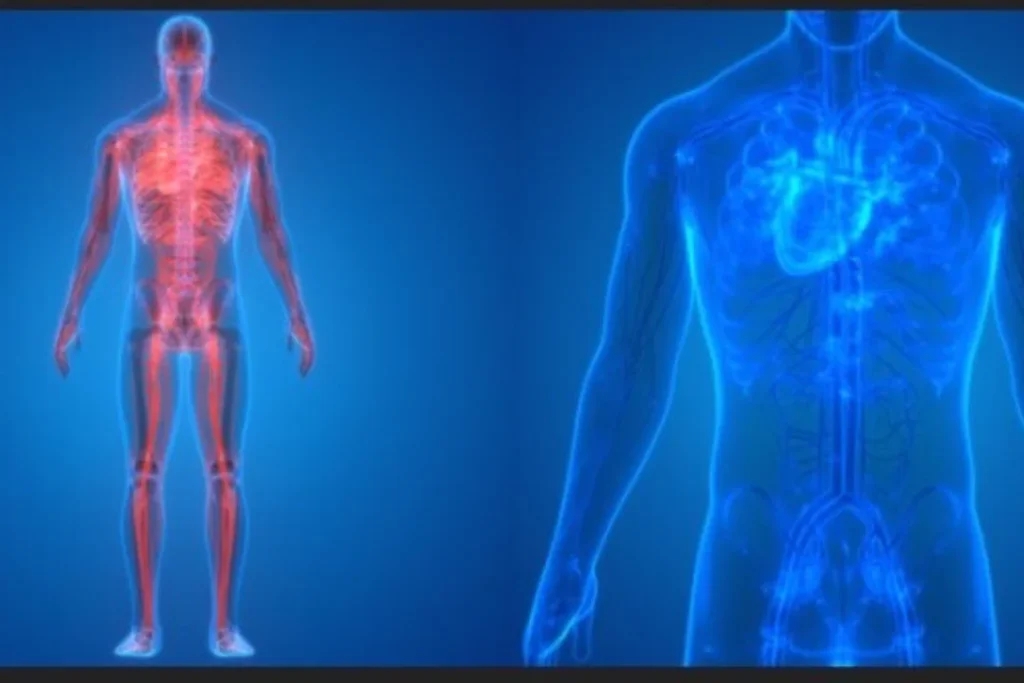

1.慢性痛・慢性症状の1番の原因は、鬱血による組織の"酸欠"

静脈の鬱血により動脈血の流入が悪くなると、組織回復のための栄養や組織が正常に働くための酸素が不足します。

それにより、神経・内臓が障害されると肩・腰・膝などにも影響が出始めます。

これは、東洋医学の身体の健康を保つ3大要素である、気・血・津液(体液)とも合致します。

現代の徒手療法も伝統医療も、血液と体液と循環を重要視しています。

循環の重要性

○血流量が大切な理由